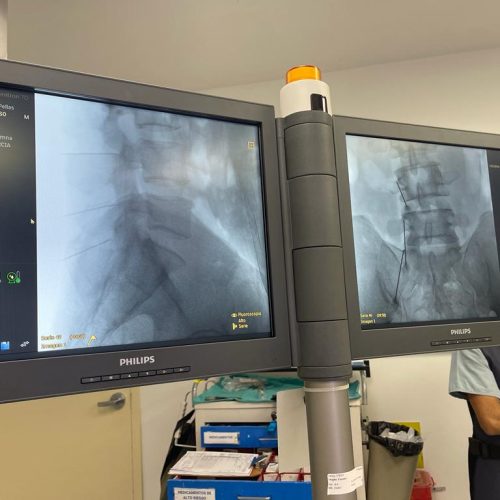

3. Rizólisis (Ablación por radiofrecuencia)

¿Qué es?

Procedimiento no invasivo que utiliza radiofrecuencia para desactivar nervios que transmiten dolor crónico en la columna.

Rizólisis (Ablación por Radiofrecuencia)

Técnica mínimamente invasiva para tratar el dolor crónico articular de la columna

La rizólisis es un procedimiento no quirúrgico que utiliza energía de radiofrecuencia para inactivar de forma selectiva los nervios responsables de transmitir dolor desde las articulaciones facetarias de la columna.